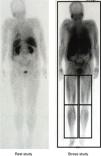

We performed tissue-muscle perfusion scintigraphy (TMPS) of the lower limbs, through one-day rest-dipyridamole protocol with 99mTc-MIBI in 24 patients, divided in two groups according to the presence of diabetes – patients with DM (Dp) 13/24 (54%), 2 males and 9 female patients, age 63±13 years and patients without DM (NDp) 11/24 (46%), 3 males and 10 females, age 61±14 years.

In the dynamic phase of the rest study, the time of maximum activity (Tmax), in the early arterial phase, of the calf region was significantly prolonged in Dp compared to NDp, with lower accumulation of the radiotracer in the 1st minute (85%/87% in Dp vs. 89%/90% in NDp, ns). 4/11 of NDp (36.4%) and 7/13 of Dp (53.8%) registered pathological value of the inter-extremity index of the calves in the stress study. Perfusion reserve (PR) of the thighs (LT, RT) and calves (LC, RC) calculated with the formula “(ROI stressROI rest)×100%/ROI rest”, was significantly lower in Dp: LT: 28±19% vs. 43±24% in NDp, p<0.05; RT: 27±17% vs. 40±25% in NDp, p<0.05; LC: 22±15% vs. 36±15% in NDp, p<0.01; RC: 25±15% vs. 38±14% in NDp, p<0.01.

This one-day protocol (rest-dipyridamole with 99mTc-MIBI) of perfusion scintigraphy of lower limbs is considered as a useful procedure in PAD assessment, especially the asymptomatic form. TMPS of the lower limbs in our study indicated that perfusion reserve in patients with DM was significantly lower, compared to the patients without diabetes.